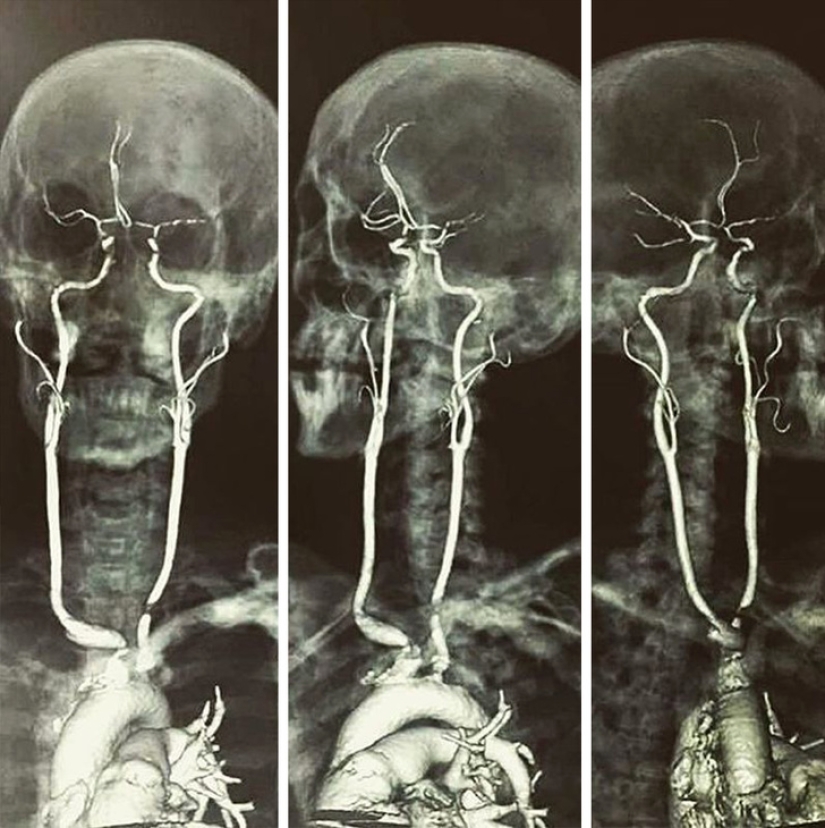

This is what the carotid arteries look like.